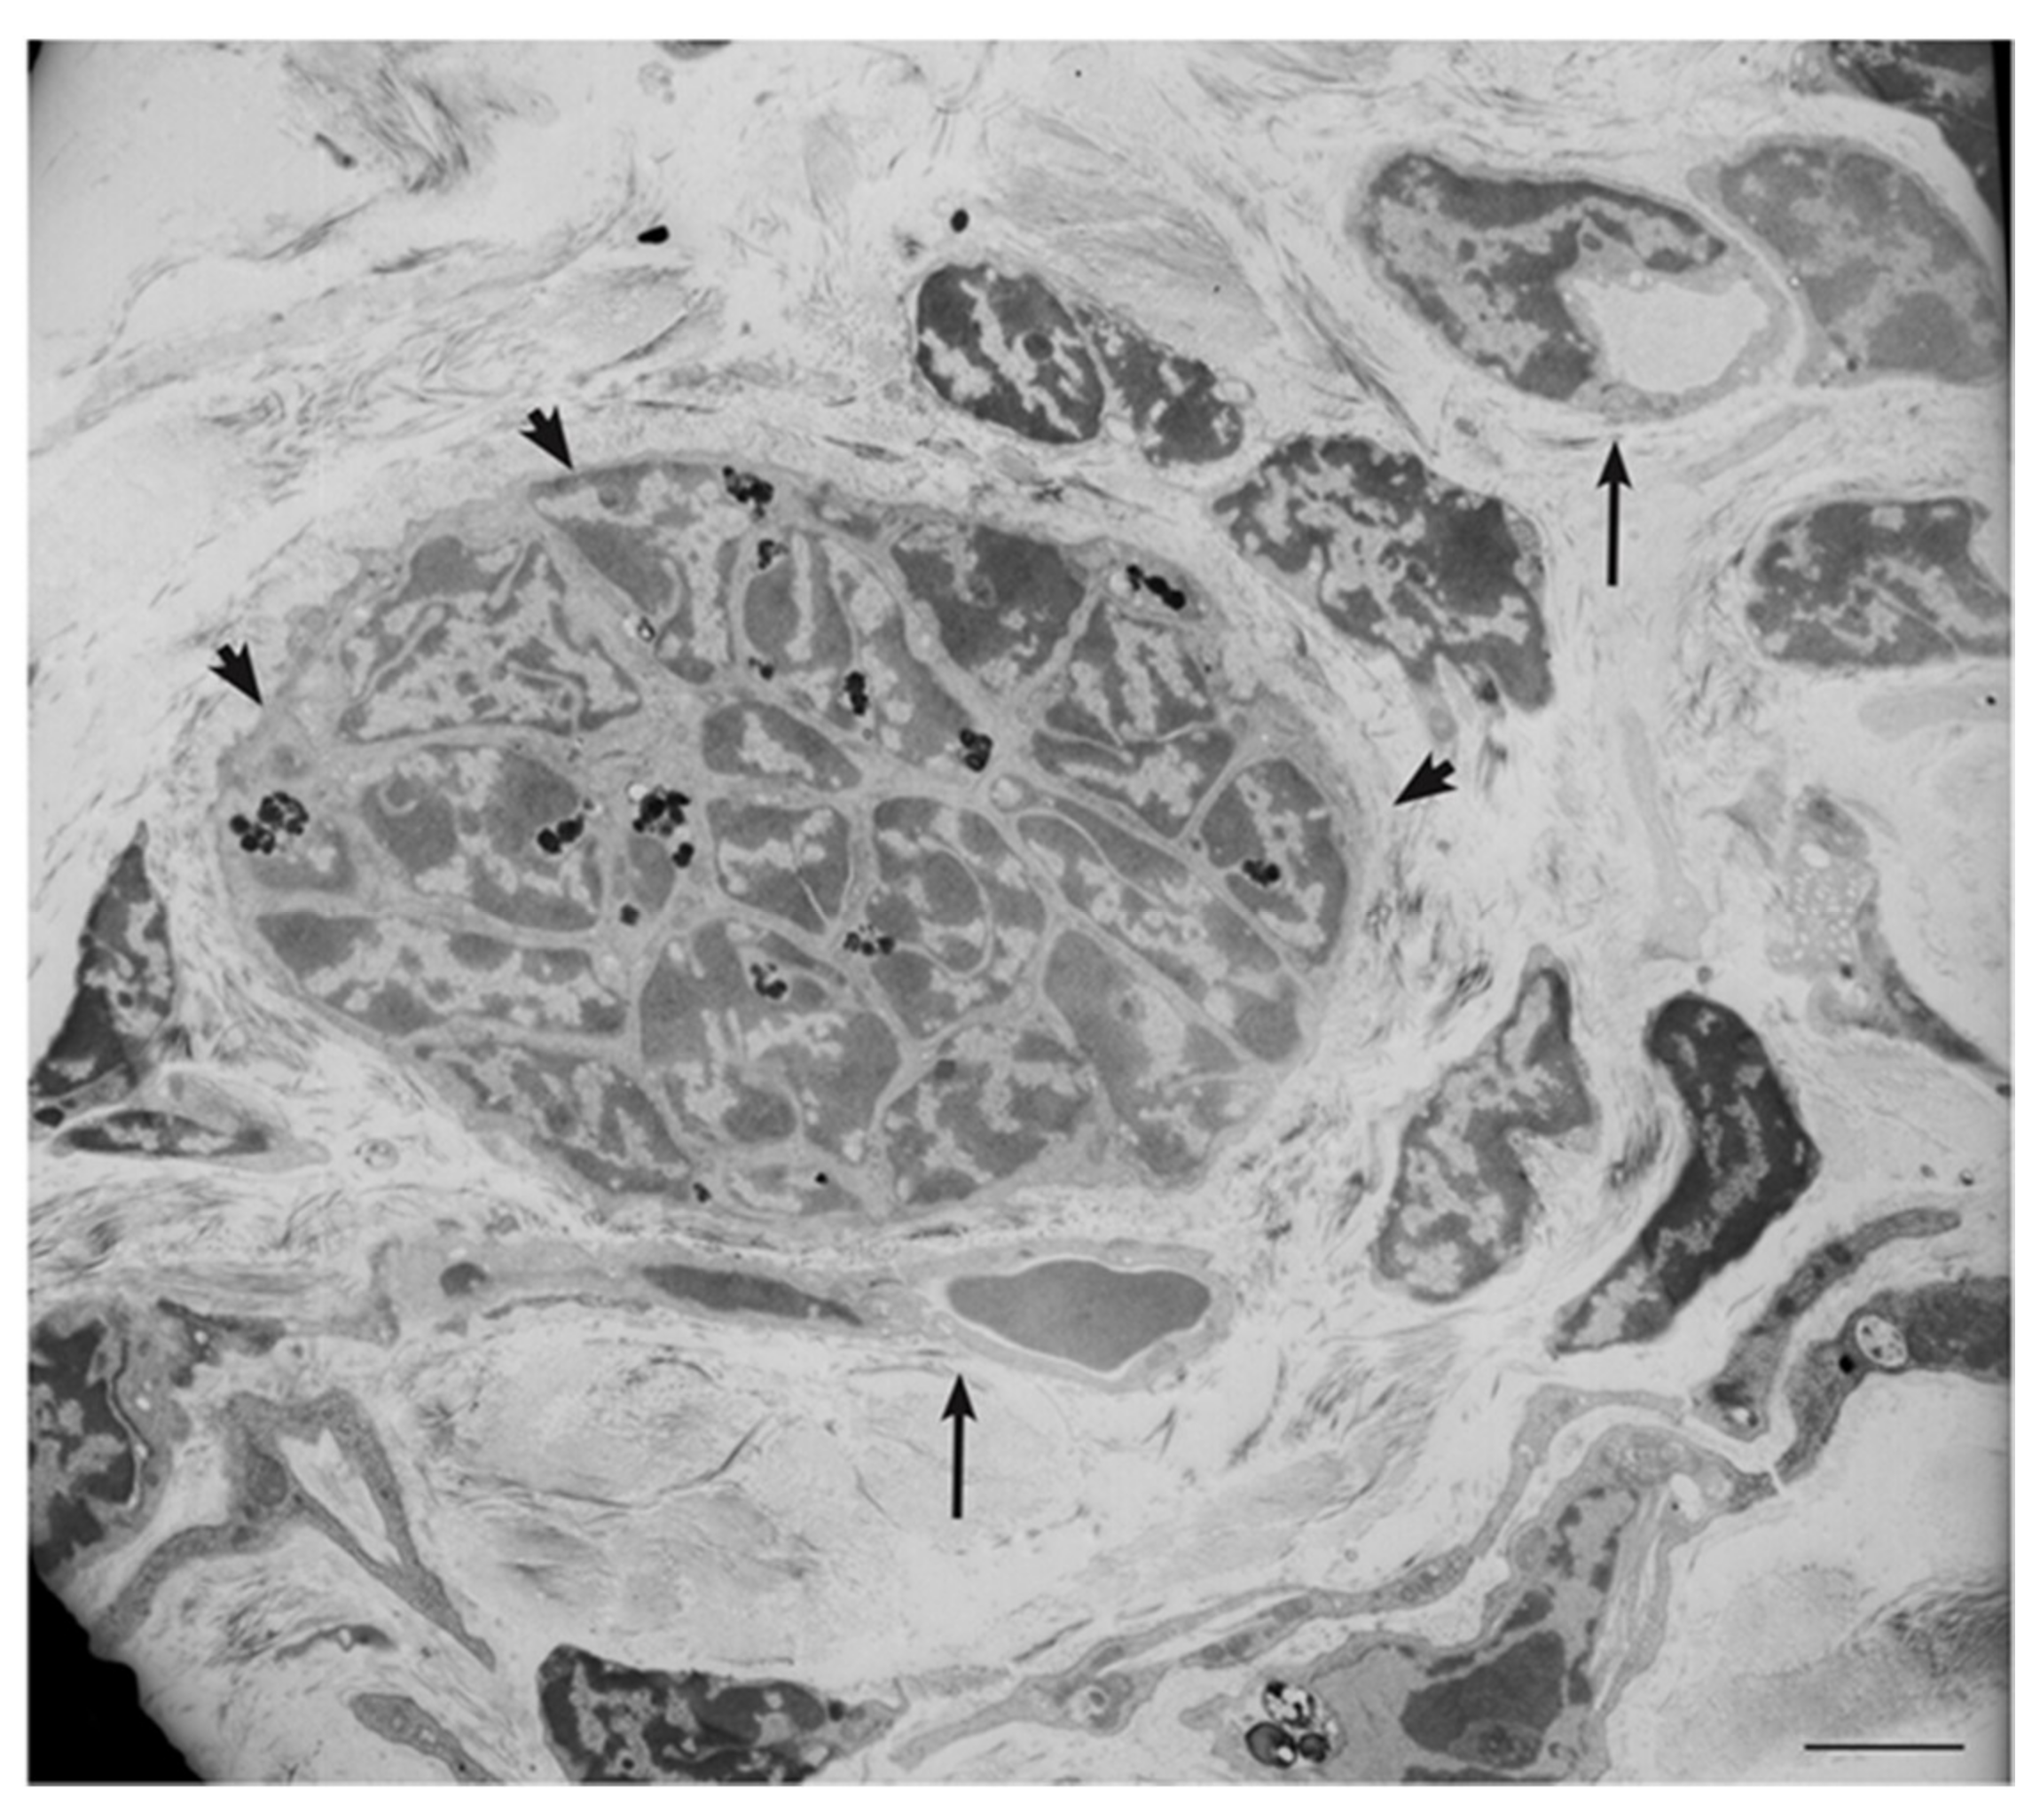

4. Ultrastructural and Immunomorphological Relationships Between the Vascular and Neural Compartments of Head and Neck Paragangliomas

5. Our Approach to the Study of Genes and Pathways Shared Among Head and Neck Paragangliomas

6. Constitutive Notch Signaling in Head and Neck Paraganglioma

10. Imatinib Blocks HNPGL Cell Growth and Inhibits Xenograft Formation